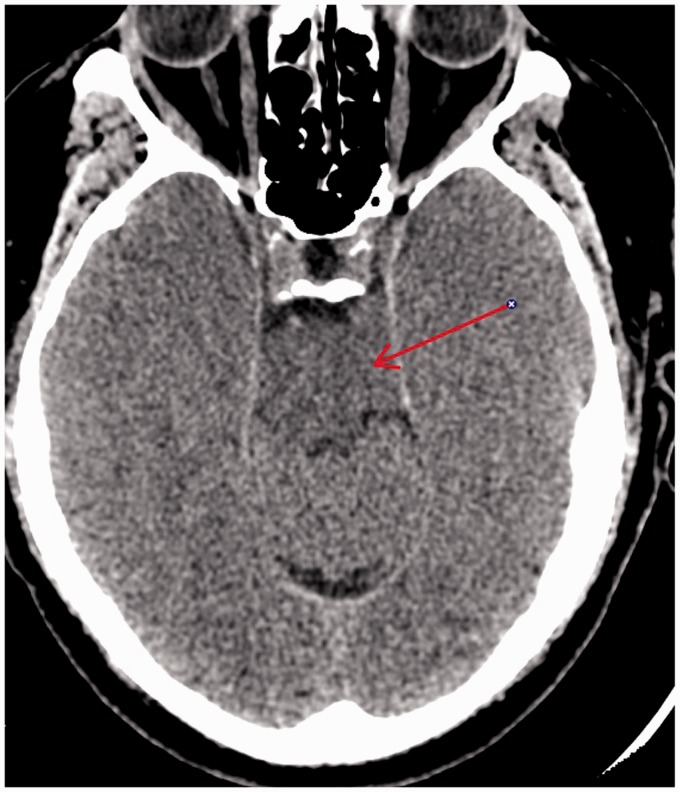

Idiopathic herniation of uncus and parahippocampal gyrus into the ambient cistern is a very rare entity, which could be mistaken for other pathology such as tumor. To the best of our knowledge, two prior cases of this kind of herniation have been described. One of these cases was with associated symptomatology and other abnormalities, and the other was characterized as idiopathic. In this case report, we report a case of accidental finding of a herniation of uncus and parahippocampal gyrus into the ambient cistern, without any other accompanying abnormalities, well depicted by magnetic resonance imaging without further necessity for surgical brain intervention.